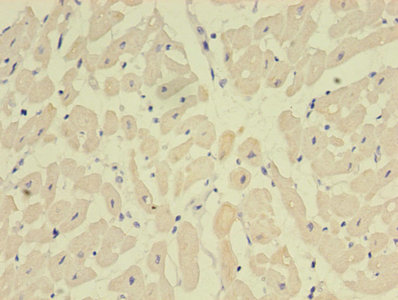

ApplicationELISA, WB, IHC, IF; Recommended dilution: WB:1:500-1:5000, IHC:1:20-1:200, IF:1:50-1:200